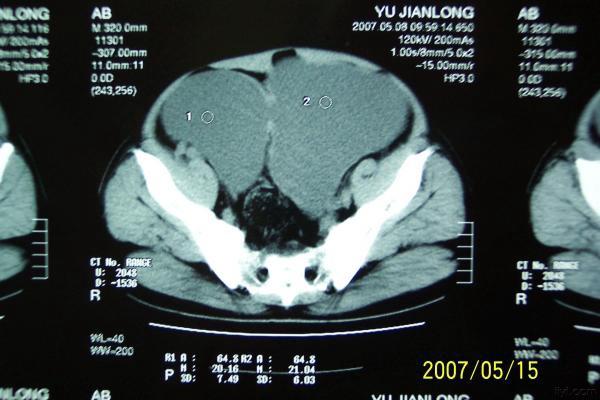

分享下一例巨大膀胱憩室的图片

分享下一例罕见病历的图片,这是我遇到的最大巨大膀胱憩室。

双膀胱,少见,要看输尿管注入膀胱的位置。

考虑双膀胱的可能性大.

双膀胱畸形